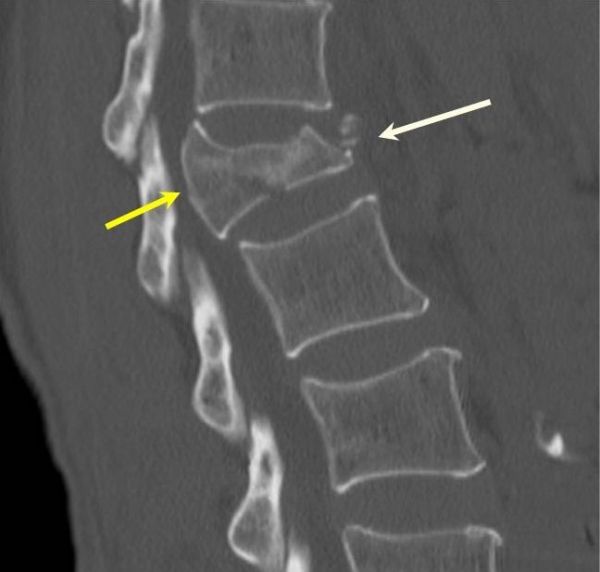

In traumatic injuries lumbar spine fractures can be associated with: pelvic or sacral fractures. intra-abdominal injuries. lower rib fractures. thoracic or cervical spine fractures. calcaneal fractures. long bone fractures or dislocations. diaphragmatic rupture / pneumothorax. In a non-traumatic setting, there are often concomitant fractures 3.